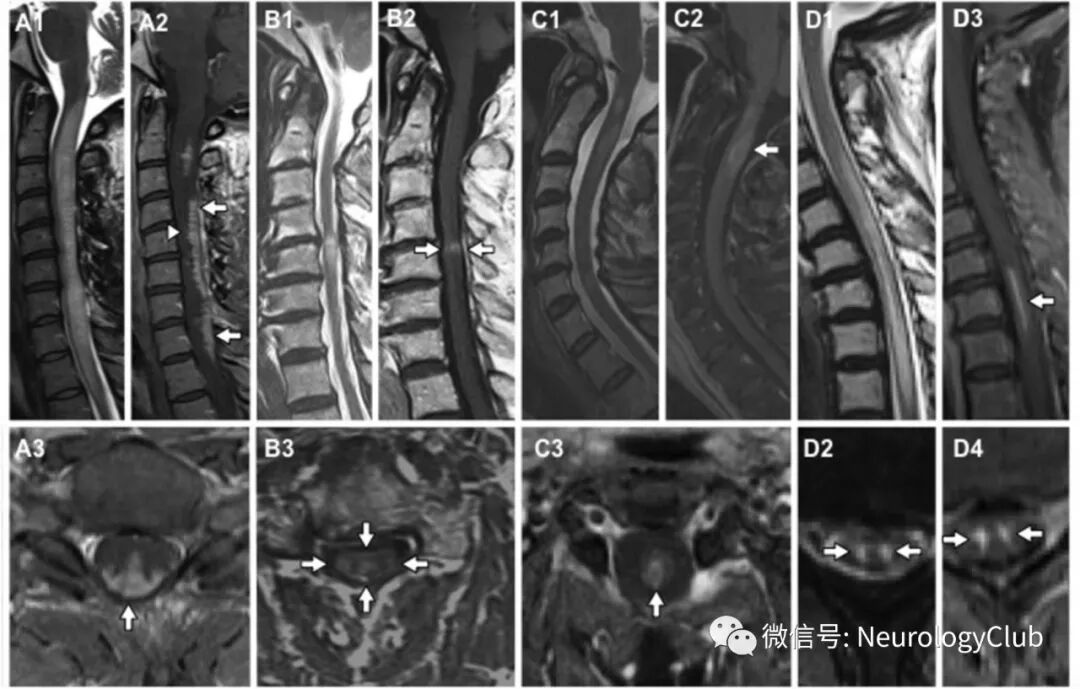

(图2:A:脊髓结节病,可见三叉戟征[A3],其由背侧软脊膜下及中央管强化形成;B:伴强化的颈椎病,可见煎饼征[B2];以及典型的中央灰质增强回避[B3];C:血清水通道蛋白-4 IgG阳性的视神经脊髓炎谱系疾病可见短节段病灶和环形强化;D:脊髓梗死可见T2WI和罕见强化的蛇眼[或猫头鹰眼]征)